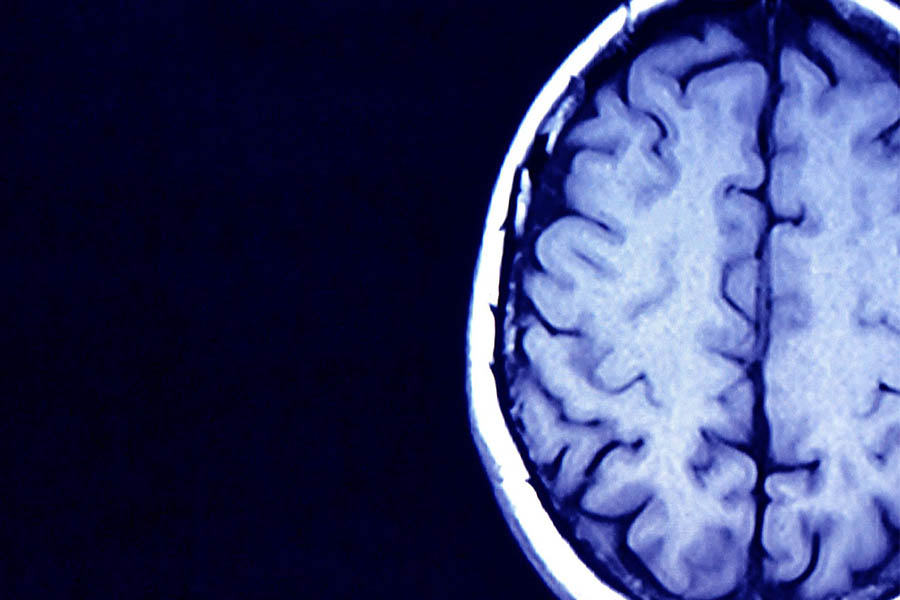

Predicting OCD Treatment Response Through Brain Connectivity Patterns

Obsessive compulsive disorder (OCD) often begins in childhood and continues throughout one’s life. It can be treated with varying degrees of success. To best optimize therapies for OCD, Dr. Kate Fitzgerald, a psychiatrist at NewYork-Presbyterian/Columbia, focused on elucidating developmentally sensitive mechanisms of exposure and response prevention (ERP) for patients of different ages. She conducted a study examining how resting-state functional connectivity and cognitive control predict symptom improvement with ERP. The goal—to gain an understanding of who will or will not benefit from ERP in order to craft the most appropriate treatment pathways.

Novel Brain Study Uncovers Four Different Autism Subtypes

In autism spectrum disorder (ASD), it is common that one individual may have vastly different symptoms from another, yet all have the same diagnosis. NewYork‑Presbyterian/Weill Cornell Medicine psychiatrist Dr. Conor Liston sought to understand the biological basis behind symptom differences and with other researchers at Weill Cornell Medicine conducted a study, leveraging machine learning, to analyze newly available neuroimaging data for patterns in brain activity and behavior. Through this work, four distinct subtypes of autism were uncovered, which might one day lead to new diagnostic methods and treatments for autism.